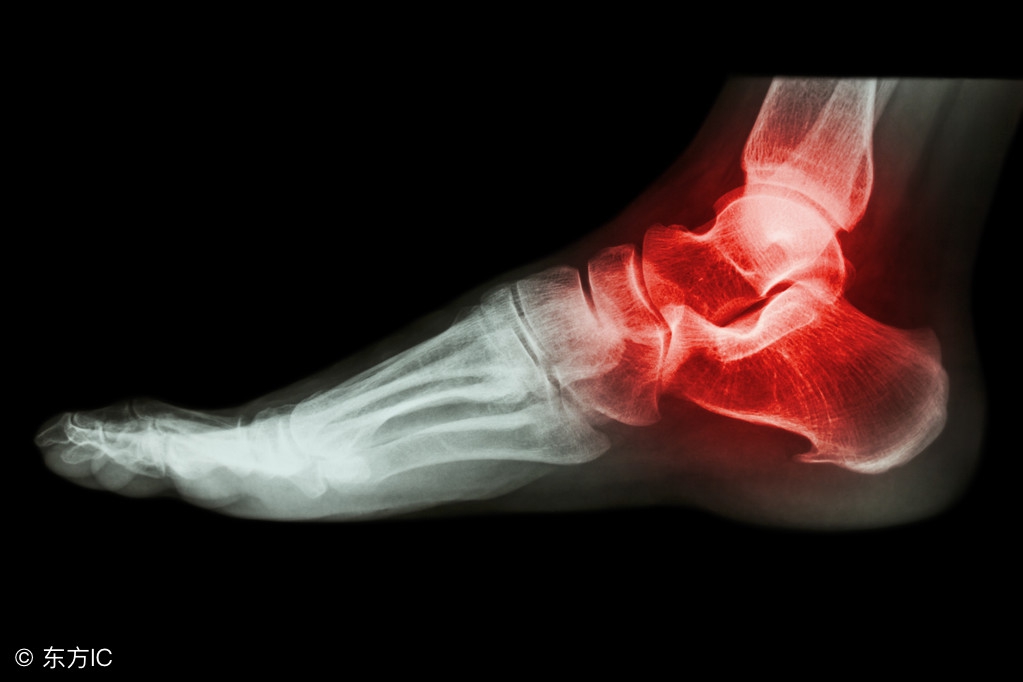

鹈鹕球员奥卡福

在季前赛中扭伤了右脚踝,

今日更新的X光检查结果显示为阴性

(无结构性损伤)

踝关节扭伤是运动损伤中发生率最高的,发生的原因大多是身体失去重心,落地时踩在别人的脚上或脚被绊倒时出现。扭伤时,局部会发生关节肿胀、疼痛,严重时甚至造成骨折。